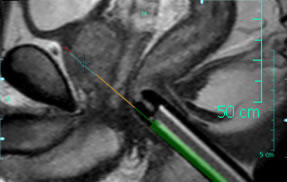

シミュレーション画像

ワークステーションでは,画像診断で良悪性の鑑別をするとともに,穿刺シミュレーションを容易に行うことができる。また,ニードルガイドは直径1cmで,超音波ガイド下で用いる経直腸超音波用プローブ(2cm以上)よりも直腸への負担が少なく,かつ腹臥位での検査が可能で,患者の負担軽減につながる。生検針はチタン製で,アーチファクトの発生を抑えて明瞭に穿刺部を確認できることから,確実な生検実施を支援する。